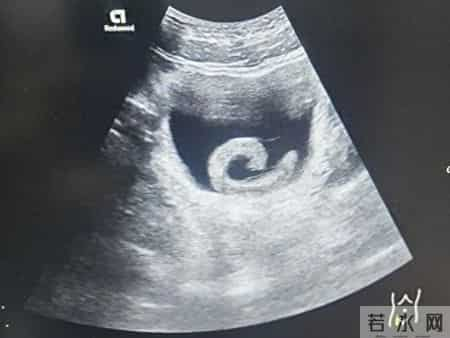

最初小郑期待某种“奇特”的效果,但很快剧烈的疼痛和排尿困难就让他清醒过来。水蛭顺着尿道向内爬行最终“安家”膀胱,开始疯狂吸血、释放抗凝血物质。小郑连忙去郑州市人民医院就诊。

泌尿外科副主任医师马曜辉为小郑实施了经尿道膀胱异物取出术,手术顺利,小郑的尿道梗阻解除疼痛瞬间消失,但回想起自己的所作所为,他只剩后怕和悔恨。